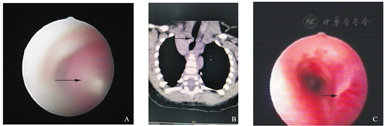

入院查体:SpO2 98%,神志清楚,口唇红,无发绀,无鼻翼煽动,咽充血,呼吸急促,频率50次/min,吸气时胸骨上窝凹陷,双肺可闻及痰鸣及明显喘鸣音。心腹可,左大腿部腘窝上方可见两处红色肿物,压之色淡,大小分别为0.5 cm×0.5 cm、0.5 cm×1.0 cm。血气分析:pH 7.378,PCO2 40.1 mmHg(1 mmHg=0.133 kPa),PO2 90.8 mmHg,HCO3- 23.1 mmol/L,BE -1.86 mmol/L,乳酸3.2 mmol/L。入院后予抗感染、布地奈德雾化混悬液+复方异丙托溴胺雾化液雾化、小剂量甲泼尼龙治疗,第2天喘息较入院稍有减轻,喉中痰响稍减少,无咳嗽,双肺仍闻及双气相喘鸣音。肺部CT:胸段气管内(距声门裂约2.6 cm)软组织密度影,考虑异物。行纤维支气管镜检查:声门下约2.5 cm膜部偏右侧可见一半圆形淡红色隆起物,表面光滑,可见小血管,长度约1.5 cm,约占管腔3/4腔隙,见图1A。肺部+心脏大血管增强CT:气管胸段见一类圆形软组织结节影,CT值约44 HU,边缘光整,最大界面约为4.6 mm×5.7 mm,增强扫描呈明显强化,各期CT值分别为167 HU(动脉期),233 HU(延迟期),局部气道明显变窄,结节影周围见小血管影与右侧锁骨下动脉起始端关系密切,见图1B。

A.治疗前支气管镜所见;B.颈部CTA ;C.治疗后支气管镜所见。

入院诊断:(1)声门下血管瘤;(2)皮肤血管瘤;(3)支气管肺炎伴节段性实变不张。患儿喘息反复,较前加剧,复查血气分析:pH 7.299,PCO2 52.8 mmHg,PO2 64.2 mmHg,HCO3- 25.4 mmol/L,BE -1.31 mmol/L,乳酸2.0 mmol/L。考虑血管瘤处于快速增长过程,存在低氧,予气管导管呼吸机辅助呼吸,并大剂量激素冲击3 d,后渐减量并停用,第5天开始服用普萘洛尔,第9天复查胸部增强CT:气管胸段软组织结节影较前略减少,大小约4.7 mm×6.4 mm×11.3 mm,增强扫描仍呈明显强化,局部气道受压变窄较前略改善。第10天停用呼吸机拔出气管导管,第12天停止吸氧,患儿呼吸平稳,无喘鸣音,少许喉鸣,肺部未闻及啰音,左大腿部腘窝上方可见两处肿物变为暗红色,生命体征平稳,第16天出院继续抗血管瘤治疗,随访中。8个月后复查支气管镜示声门下血管瘤明显消退,见图1C。